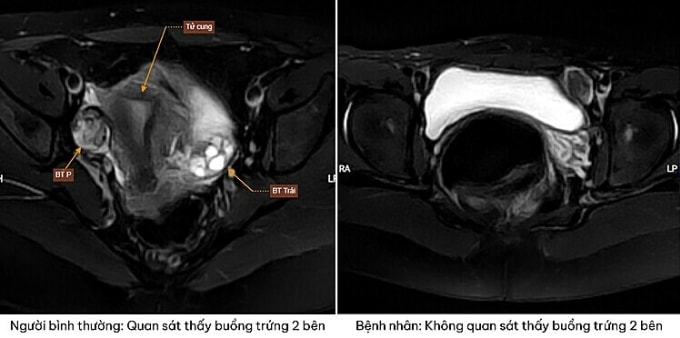

Kết quả siêu âm và chụp cộng hưởng từ (MRI) cho thấy bệnh nhân không có tử cung và buồng trứng hai bên. Thay vào đó, tại vùng hạ vị (bụng dưới), các bác sĩ phát hiện khối tổ chức nghi ngờ là tinh hoàn lạc chỗ. Tiếp tục xét nghiệm nhiễm sắc thể đồ, kết quả khẳng định bệnh nhân mang bộ nhiễm sắc thể 46, XY thuần. Điều này xác định người bệnh là nam giới về mặt di truyền dù sở hữu hình thái bên ngoài của nữ.